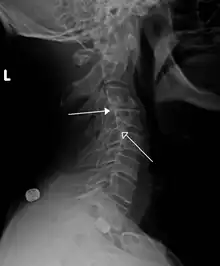

| Grade 1 retrolistheses of C3 on C4 and C4 on C5 | |

A retrolisthesis is a posterior displacement of one vertebral body with respect to the subjacent vertebra to a degree less than a luxation (dislocation). Retrolistheses are most easily diagnosed on lateral x-ray views of the spine. Views where care has been taken to expose for a true lateral view without any rotation offer the best diagnostic quality.

Since the vertebral body in a retrolisthesis moves in a posterior direction, the grading used for spondylolistheses is of little use. It is however useful to divide the anterior to posterior dimension of the intervertebral foramina (IVF) (4) into four equal units. A posterior displacement of up to ¼ of the IVF is graded as Grade 1, ¼ to ½ as Grade 2, ½ to ¾ as Grade 3, ¾ to total occlusion of the IVF as Grade 4. Alternatively, a measurement of the amount of displacement can also made by measuring the bone displacement in millimetres.